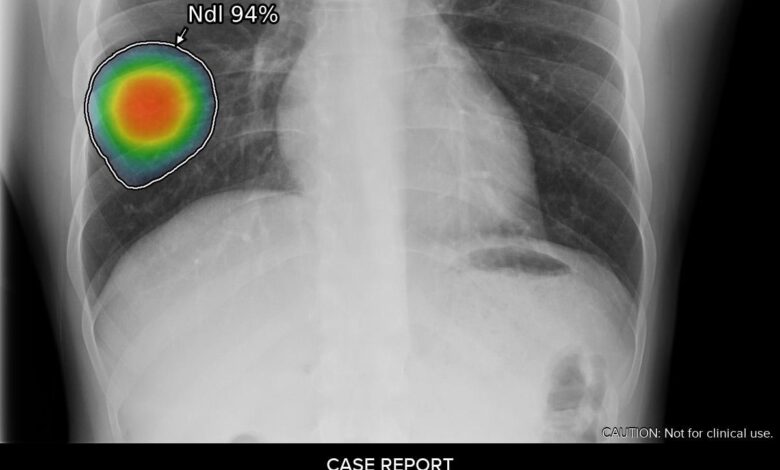

GE Healthcare Launches New AI Suite to Detect Chest X-ray Abnormalities

… Including Pneumonia Caused by COVID-19 & Tuberculosis GE Healthcare continues to provide tools to support clinicians in today’s COVID-19 environment GE Healthcare introduced its Thoracic Care Suite, a collection of eight artificial intelligence (AI) algorithms from Lunit Insight CXR to help alleviate clinical strain due to COVID-19. The AI suite quickly analyzes chest x-ray findings and flags abnormalities to…